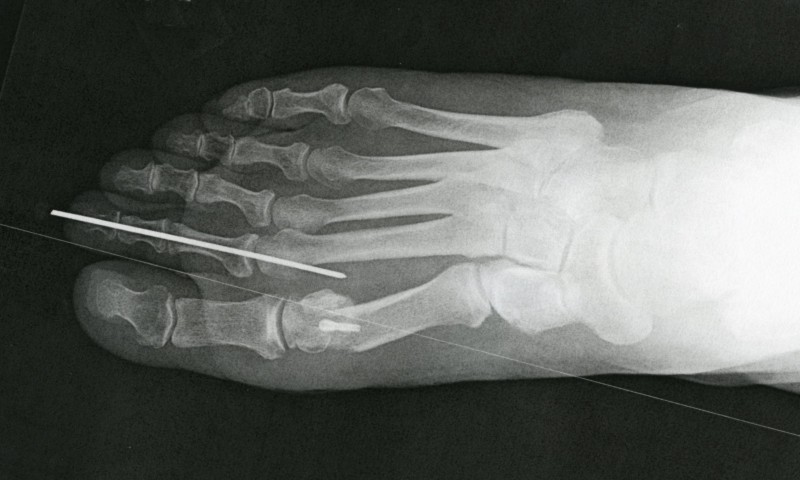

At the second post-op, three weeks later, when the X-ray

showed satisfactory progress, the pin was removed, an effort much like pulling a nail out of a board with pliers.